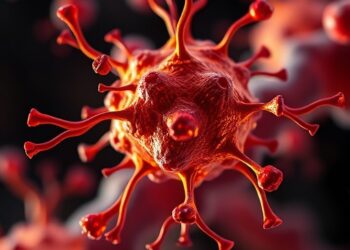

Speeding Up Chikungunya Vaccine Development in Africa: Introducing the ACT-CHIK Project

In a groundbreaking advancement poised to reshape public health landscapes across Africa, the Institut Pasteur has unveiled the ACT-CHIK initiative—an...